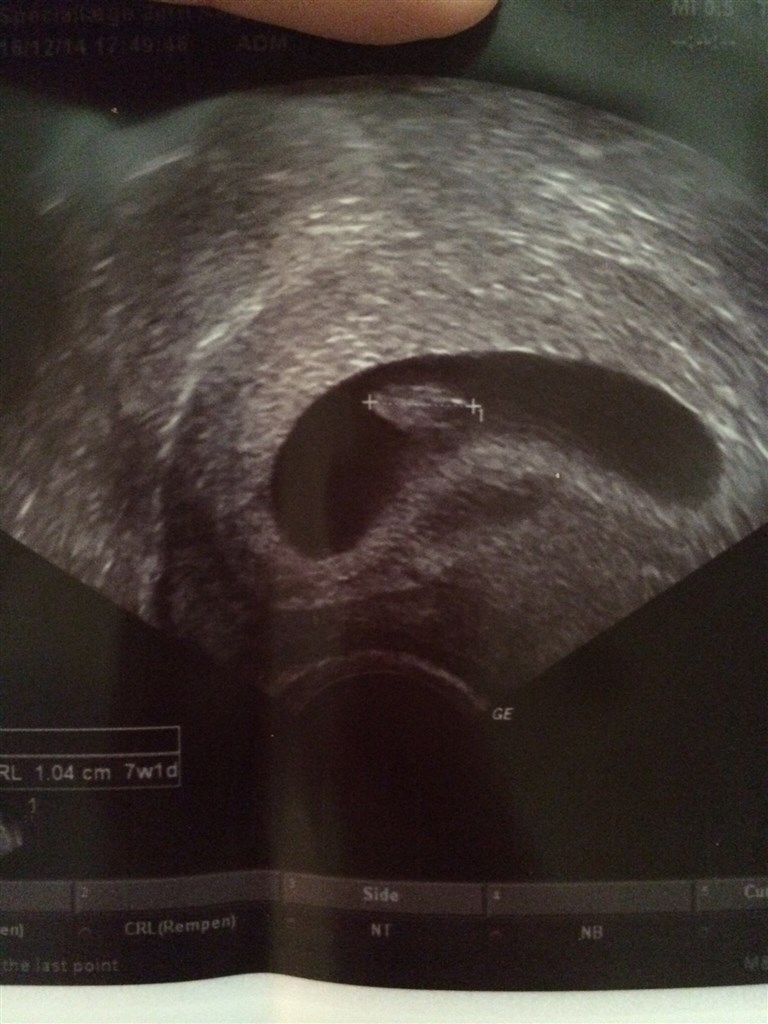

Var til ultralydsscanning idag, er 7+1 henne. Det var helt fantastisk at se den lille for første gang selvom det bare ligner en lille peanut

Det var helt uvirkeligt at se hjerteblink og vi hørte også hjertelyden ❤️ Helt fantastisk!!